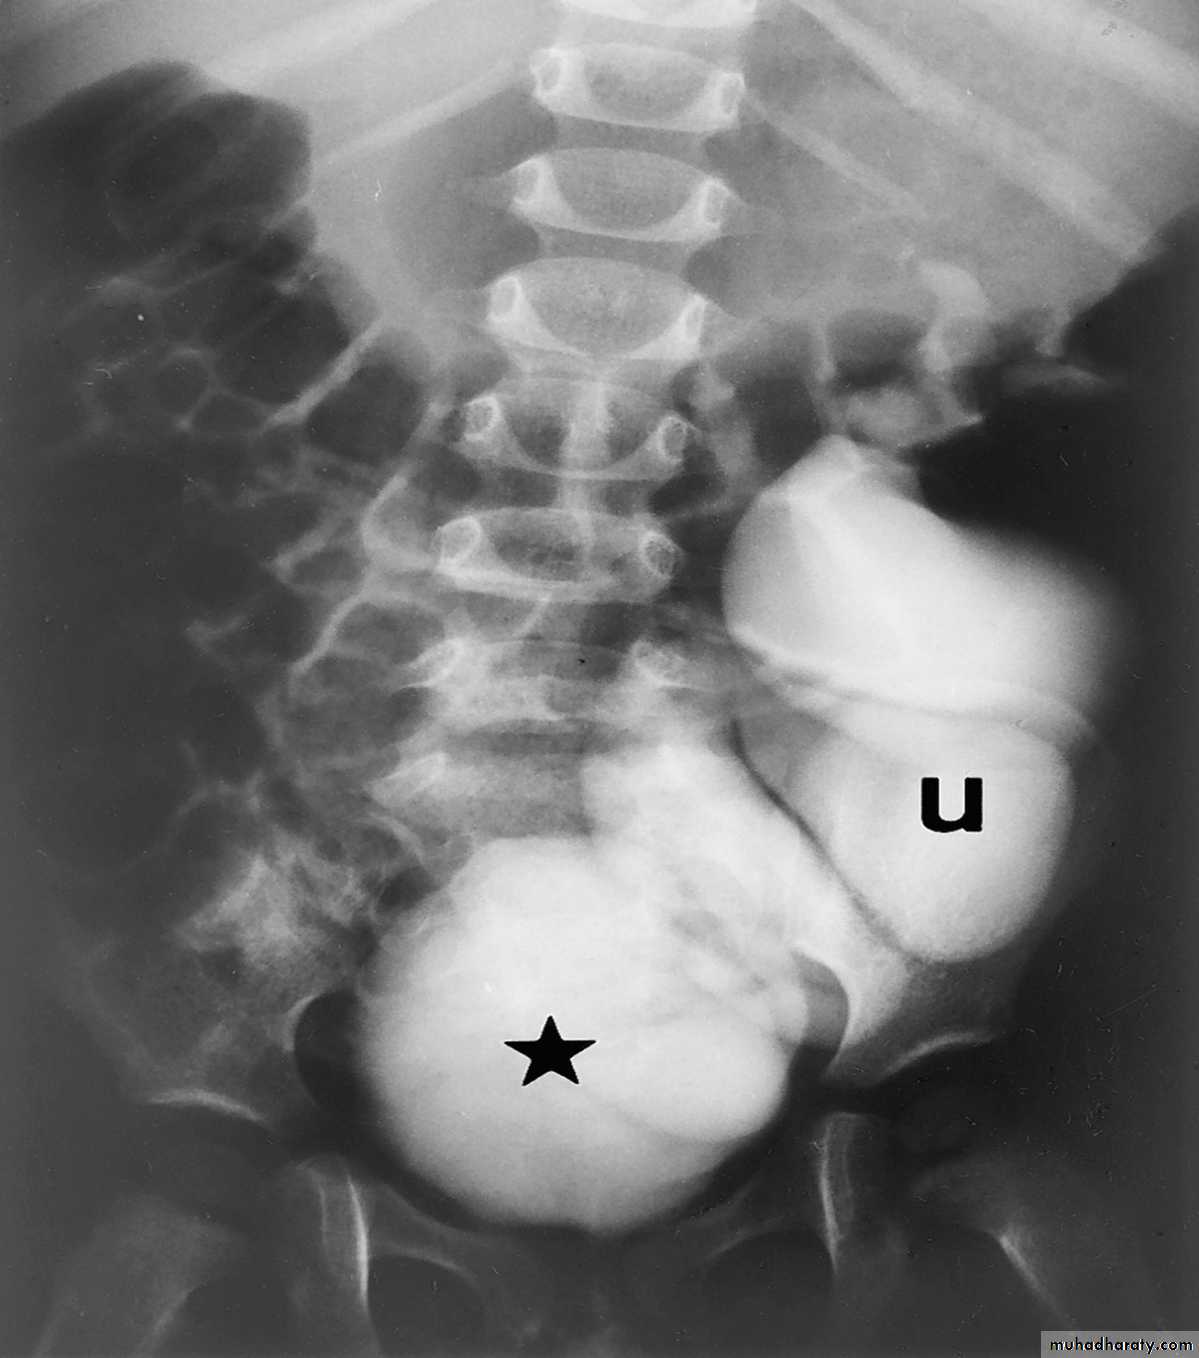

*Right kideny is ectopic(presacrally located)&bilateral hydronephrosis.